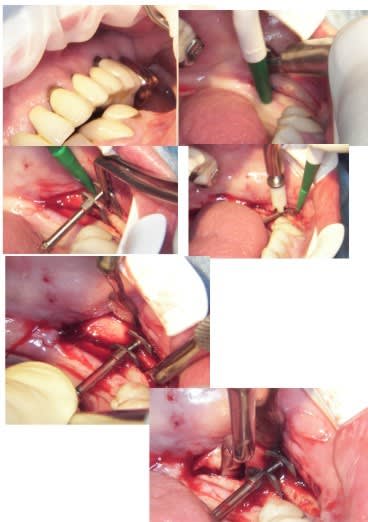

> Pourquoi svp ? en réalité c'était surtout de la condensation, seul pour la crête sup de l'os 42/32/32 j'ai fait une incision de décharge pour protéger la berge linguale, il aurait été plus sage de mettre un implant en 33 pour l'équilibre mais Béotien avait peur que j'abime la crosse du foramen, donc j'ai été moins invasif car je n'ai pratiquement rien foré, 0;75 mm en initial, ensuite condensation avec les condenseurs et aussi le piezo pour les parties très corticales qui résistaient aux expanseurs et finition au foret 3,5 pour l'apex, le tout à 49 t/mn sans irrigation.

> Ce n’est pas la même chose avec des forets d'expansion ? Non cas ce ne sont pas des forets, mais des condenseurs, tu repousse l'os et les artérioles

> Tu as placé quoi comme implants ? (diam + long) 3,5 x 13mm

pour ce vendredi, expansion verticale en bas à gauche, pas simple mais...

Implants à gauche et à droite, c’est un cas d’expansion horizontale droite et gauche que je dois faire en Novembre en directe (pour des confrères Russes), et vendredi je prépare le site à gauche, pour avoir une hauteur correcte pour remplacer ensuite 35/36.37.

En principe je ne poserais pas les implants vendredi, sauf si le site est nickel pour.